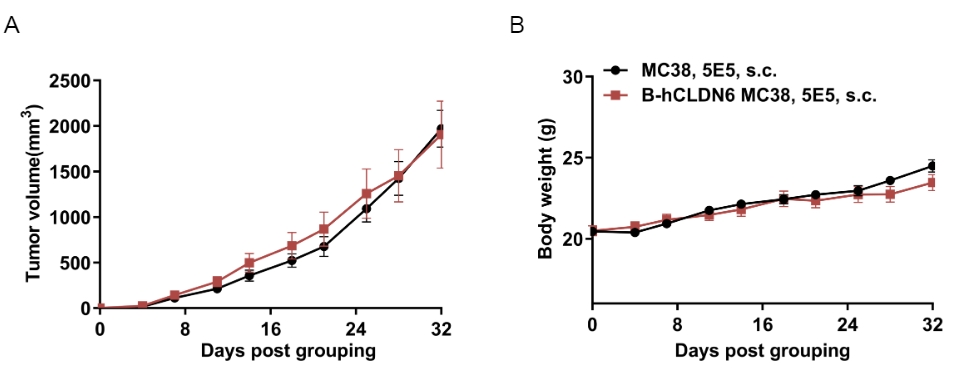

Subcutaneous homograft tumor growth of B-hCLDN6 MC38 cells in B-hCD16A mice.

B-hCLDN6 MC38 (5x105) and wild-type MC38 cells (5x105) were subcutaneously implanted into B-hCD16A mice (female, 8-week-old, n=8). Tumor volume and body weight were measured twice a week. (A) Average tumor volume ± SEM. (B) Body weight (Mean± SEM). Volume was expressed in mm3 using the formula: V=0.5 × long diameter × short diameter2. As shown in panel A, B-hCLDN6 MC38 cells was able to establish tumors in B-hCD16A mice and can be used for efficacy studies.